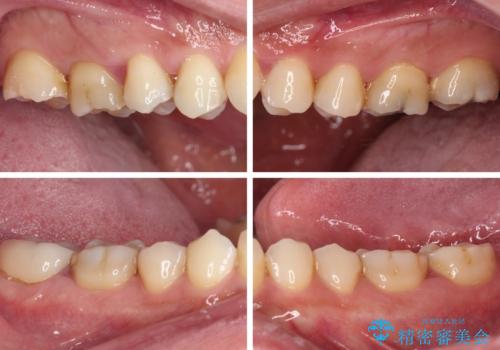

まずは仮歯に置き換え、歯周ポケットを除去するための外科処置(歯肉弁根尖側移動術)を行い、治癒を待ってセラミッククラウンにて補綴治療を行うこととしました。

外科処置後は知覚過敏症状が酷くなることが多いのですが、術後は比較的落ち着いており、スムーズに処置を進めることができました。